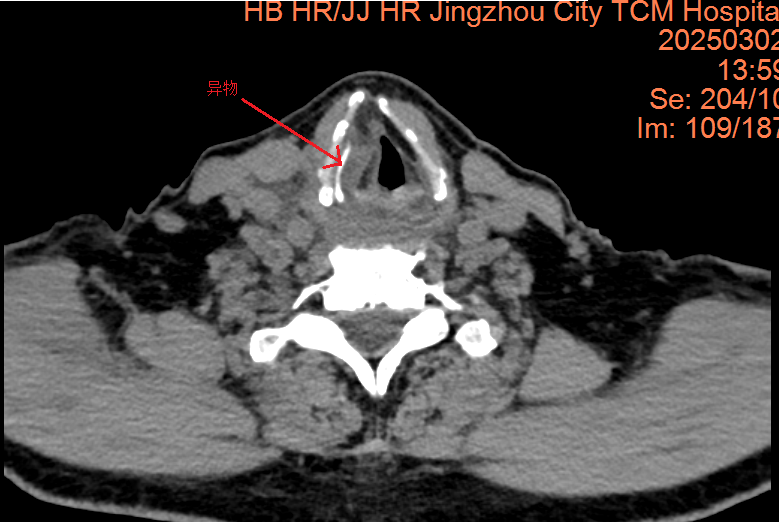

这名73岁的男性患者因误食鱼刺导致咽痛、吞咽困难和声音嘶哑长达三天,并在外院接受抗炎治疗后未见好转,随后紧急转入荆州市中医医院。入院检查发现,鱼刺呈“S”形嵌顿于右侧声门旁间隙,长度约3cm,周围组织严重水肿。此外,患者电子喉镜提示急性会厌炎及声带麻痹,随时可能引发窒息或致命性感染。

面对高龄、基础疾病(高血压)及复杂解剖粘连等风险,耳鼻咽喉头颈外科主任刘燕青带领的团队迅速制定了详细的手术方案。先行食管镜探查定位异物,发现梨状窝黏膜破损,异物被炎性组织紧密包裹,无法以内镜方式安全取出。团队果断转为颈侧入路切开取刺,沿右颈作3.5cm切口,逐层分离颈阔肌、带状肌,切除部分甲状软骨板,暴露声门旁间隙,术中见鱼刺穿透黏膜,团队采用“钝性剥离+分段剪断”策略,分三段取出长约3cm的鱼刺,并进行了穿孔黏膜的缝合修复。术后,患者接受了包括抗感染、抗炎、护胃、雾化、降压、营养支持及中医康复在内的综合治疗。复查时,食管钡餐造影未见造影剂渗漏,患者康复情况良好,已康复出院。